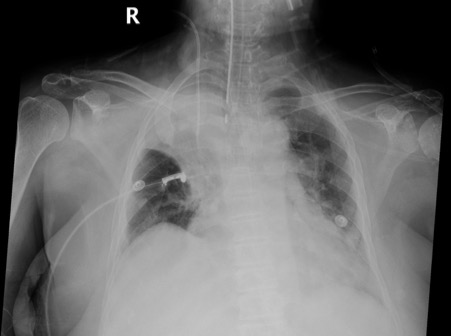

History: Patient with cervical carcinoma admitted in the ICU with urosepsis.

This is a frontal chest radiograph. (As a routine, prefer to say frontal rather than AP or PA as then the discussion could go tangentially!.. In this case of course this is a supine AP film as it is an ICU patient).

The medial end of the right clavicle is away from the sternum as compared to the left, denoting positive rotation in this radiograph. Hence, it is a Right posterior oblique view of the chest. (You can see another example explaining rotation here)

There is right upper zone consolidation collapse. The right transverse fissure is pulled up with the convexity facing up, along with tenting of the right hemidiaphragm. These features are suggestive of volume loss (collapse) involving the right upper lobe.

The positive rotation limits the evaluation of tracheal or mediastinal shift.

The right costophrenic angle is clear.

There is mild left hilar prominence, along with left lower zone obliterating the left costophrenic angle.

The cardiothoracic ratio is around 60% with evidence of left ventricular enlargement.

The tip of the right jugular line is in the region of the superior vena cava. The tip of the ET tube is approximately 4 cm proximal to the carina. Endoenteric tube is present but the tip is not visualized.

In the given setting of urosepsis, findings are consistent with an infectious etiology. Do note that if this was an OPD x-ray, an underlying right upper lobe malignancy should have been suspected.